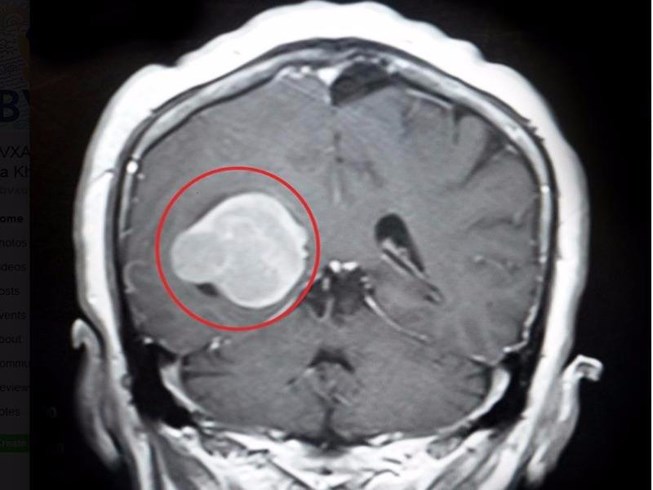

U màng não là những khối u phát triển chậm ở màng bao phủ não, tủy sống và rễ Thần kinh tủy sống (màng não). Hầu hết u màng não là u lành tính (không phải ung thư). Khoảng 80% bệnh nhân U màng não được chữa khỏi nếu khối u được loại bỏ hoàn toàn.

Click vào ảnh để xem 4 hình ảnh minh họa

Nếu bạn có khối u màng não nhỏ, phát triển chậm và không có triệu chứng. bạn không cần điều trị đặc biệt nhưng sẽ được chụp cắt lớp (CT) hoặc chụp cộng hưởng từ (MRI) thường xuyên để theo dõi mức độ phát triển của khối u.

U màng não có thể được chẩn đoán dựa trên bệnh sử và khám thực thể. Bác sĩ sẽ yêu cầu chụp cắt lớp (CT), chụp X-quang hoặc cộng hưởng từ (MRI) não. Bác sĩ có thể thực hiện một phương pháp khác như chụp mạch máu trong não (mạch não đồ) nếu cần phẫu thuật.